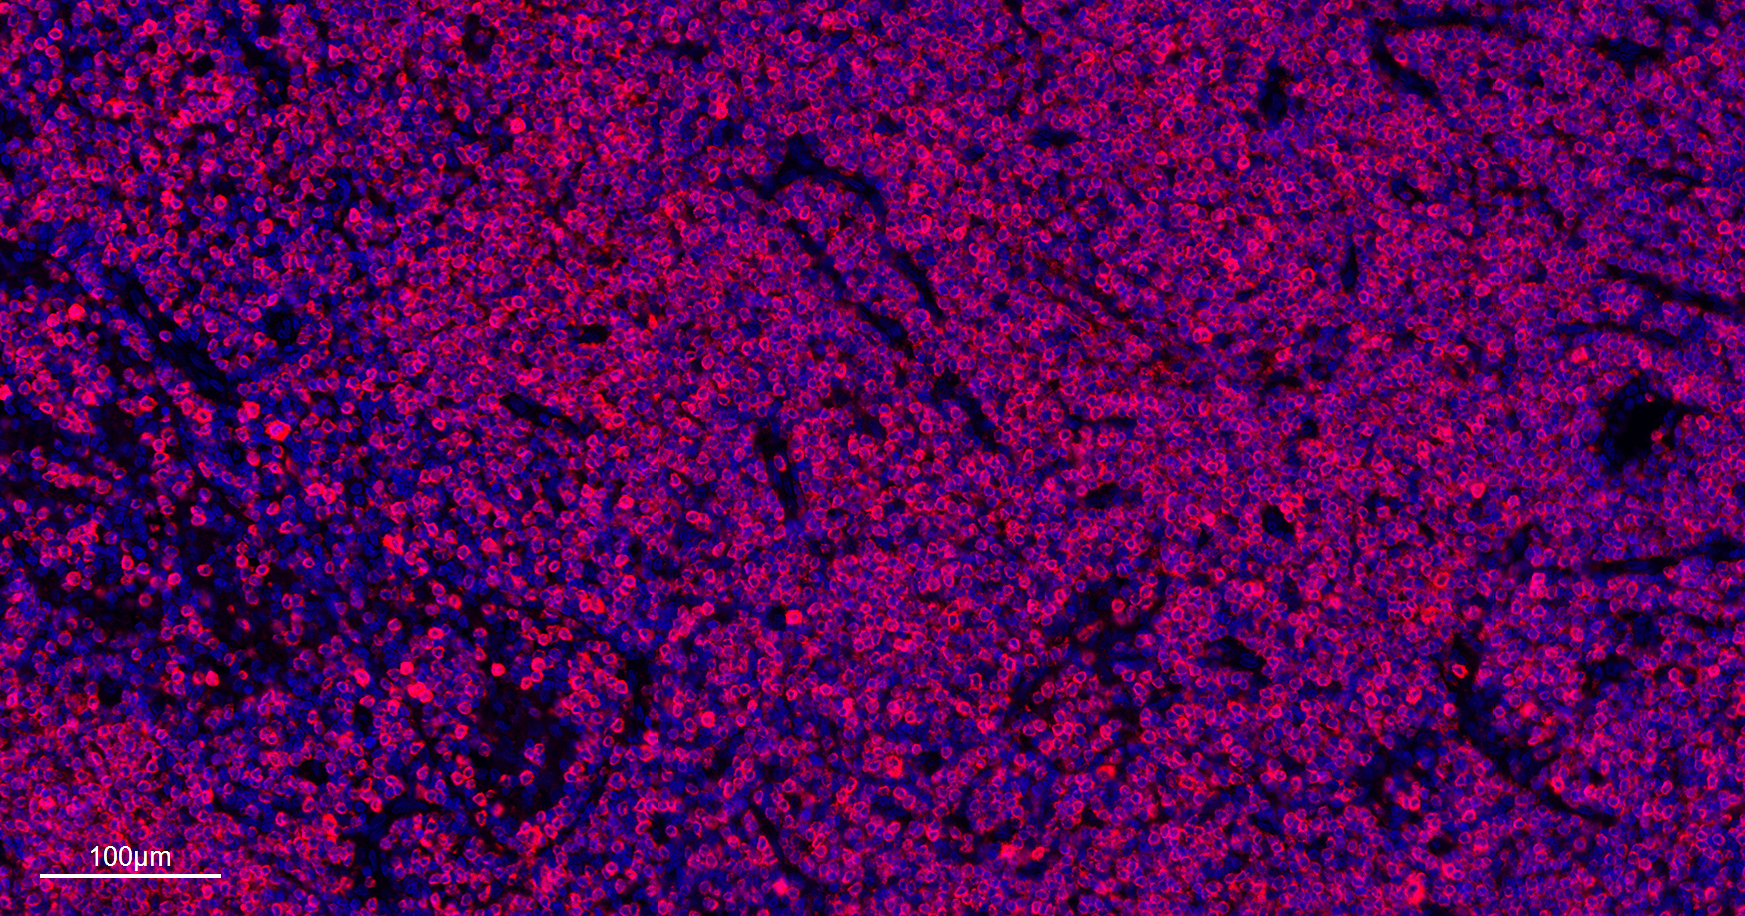

| IF |

1:200-1000 |